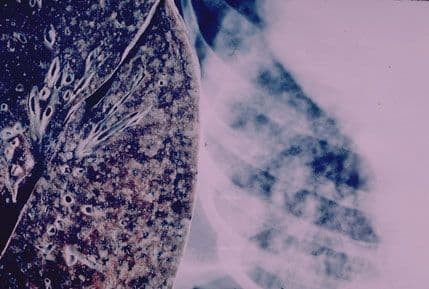

Stručnjaci upozoravaju da je tuberkuloza među zaraznim bolestima drugi najčešći uzrok smrti u svijetu, posle AIDS-a. SZO procjenjuje da će do 2015. godine oko dva miliona ljudi u svetu biti zaraženo tuberkulozom otpornom na lijekove.